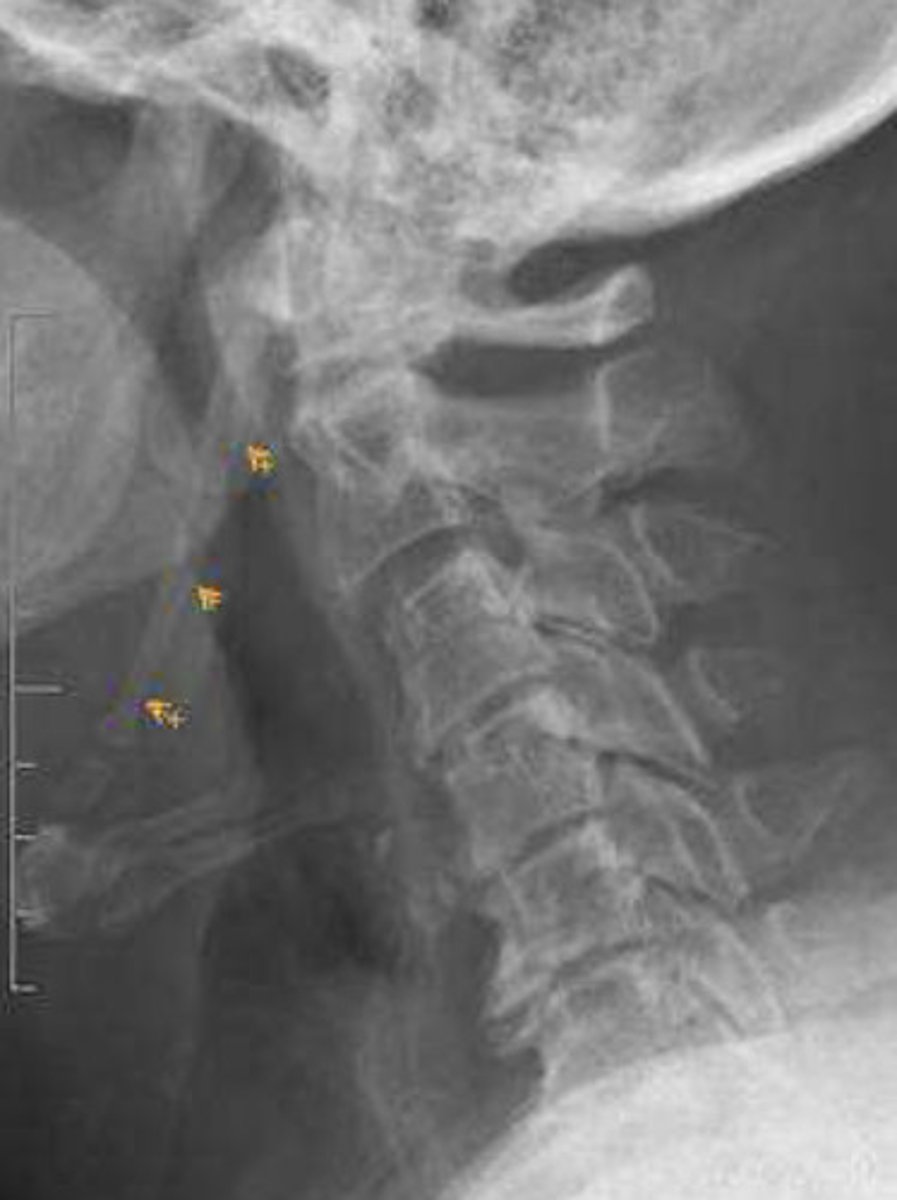

Each cervical vertebrae transverse processes are formed by the lateral extension of the center of the neural arches

The costal portion of the transverse process may enlarge and elongate the anterior tubercle to articulate with the vertebrae below, giving rise to an unusual variant that could simulate a fracture